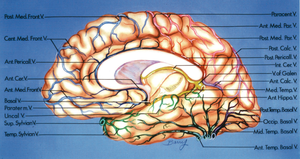

A. Cerebri posterior

A.cerebri posterior (ACP) forsyner den mediale del af den inferiore plade og den mesiale flade af temporallappen. A. cerebri posterior er den terminale forgrening af a. basilaris hvor P1 stykket forløber fra basilaris toppen til det punkt hvor a. communicans posterior forbinder ACP med a. carotis. Dette sted markere overgangen til P2-stykket, som forløber rundt om lateralsiden af hjernestammen. Fra P1-sykket, altså foran hjernestammen afgår a.choroidea media posterior som herefter forløber rundt om hjernestammen medialt for P-2 & P3-stykket. Den posterior mediale a. choroidea i sit forløb grene til hjernestammen, samt forsyner plexus choroideus i III. ventrikel og del af lateral ventriklen. Endvidere afgår de thalamostriate grene fra ACM ligeledes fra P1-stykket og løber ind i hjernen gennem substantia perforata posterior. Endvidere afgives grene til tectum, tegmentum og den cerebrale pedunkel. P2 afgiver grene der forsyner den inferior og den mesiale flade af temporallappen. P3 grene udgøres af a.calcarina og parieto-occipitalis. A. calcarina forløber i en stor del af sit forløb i sulcus calcarinus. P2 afgiver også a. choroidea postrior lateralis som udover at forsyne plexus choroideus i lateral ventriklen også kan forsyne dele af den cerebrale pedunkel, dele af crura of corpus af fornix, corpus geniculatum laterale, pulvinar, nucleus dorsomedialis af thalamus og corpus af nucleus caudatus. Læsion af ACP og dennes grene er således en potentiel risiko ved kirurgi sv.t. den inferior temporallap posteriort eller i cisterna ambiens.

Venøs drænage

Den venøse drænage udgør i vid udstrækning et anastomoserende netværk med betydelig individuel variation i størrelse og forbindelse mellem de enkelte dræneringsveje. De tre hoved dræneringsveje er mesialt via basal vein of Rosenthal som bag hjernestammen drænerer til v. Galeni og videre til sinus rectus. Anteriort via sylvian veins som drænerer til sinus sphenoparietale (via hvad der ofte kaldes lateral fissurens brovener). Lateralt dræneres til tentoriegruppen af vener hvor af den største ofte er v. Labbé. Disse tre drænerings netværk anastomosere, og ingen af disse er a priori uden risici at dele. Så der gælde samme mantra for venres som for arterier, de skal i videst mulige omfang bevares med mindre det kirurgisk mål er at fjerne hele deres forsynings og dræningsområde, som eksempelvis ved lobektomier.